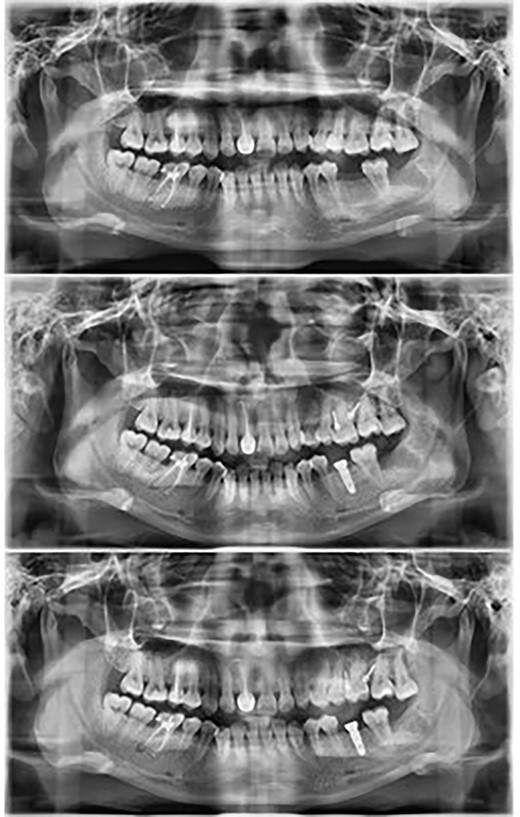

Maxillary molar intrusion 4 mm above the occlusal plane (Fig. 3).

Panoramic radiographs recorded at regular intervals showed that the lamina dura around the molar was intact and no root resorption was observed.

Panoramic radiographs show the intrusion process along with placement of the implant in the opposing arch.